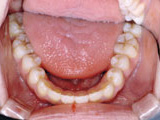

症例1:乱ぐい歯「歯並びが乱れている」

治療前